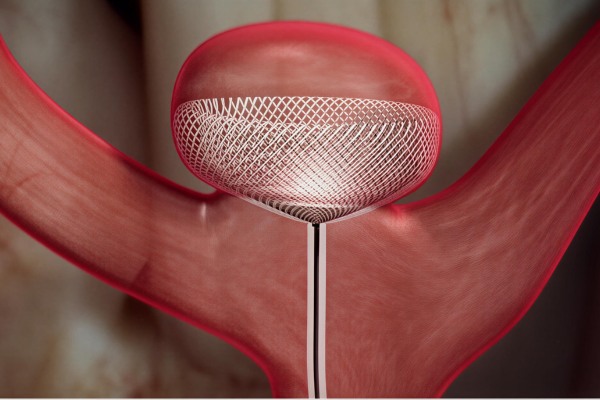

Enhances treatment by redirecting blood flow away from the aneurysm, promoting gradual healing, improving vessel stability, and ensuring stronger, durable protection against future rupture.

Flow diverter treatment is a minimally invasive procedure used to treat complex brain aneurysms that are difficult to manage with surgery or coiling. It is commonly recommended for wide-neck or hard-to-reach aneurysms.

A special device is placed inside the parent artery to redirect blood flow away from the aneurysm, allowing it to heal naturally while maintaining normal brain circulation.